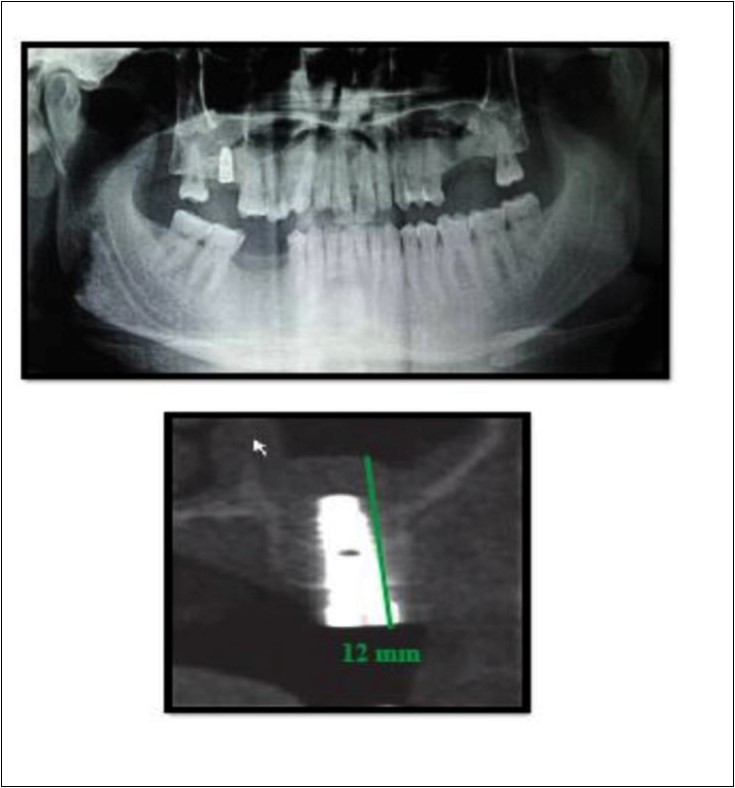

Case Report 3

A 75 year old man reported to the unit seeking options for replacement of his missing upper right first molar with fixed prosthesis. Due to the residual bone height of 5.3 mm, the patient was advised and subsequently, underwent the procedure of indirect sinus elevation using sinus osteotomy in relation to 16 region followed by placement of a dental implant measuring 5 mm x 10 mm under local anesthesia and strict aseptic protocols. The implant was allowed to osseo-integrate for a period of six months during which the patient was followed periodically. At the end of 6 months, a CBCT scan showed an increase in bone height to 11.5 mm. (Figure 5)

Figure 5.Pre-operative and post-operative Orthopantomographs and cross sections of CBCT showing residual alveolar bone height

Case Report 4

A 19 year old young woman was referred to Department seeking options for rehabilitation of missing right upper first molar with fixed prosthesis as she was uncomfortable with the removable partial denture in relation to 16. The residual bone height in region was 4 mm in 16 tooth region. Patient was taken-up for direct sinus elevation via lateral window approach for sinus augmentation in relation to 16. Under aseptic conditions and local anesthesia, lateral wall of maxilla was exposed after muco-periosteal flap elevation. A window was created of 1cm diameter corresponding to apical aspect of 16. Sinus membrane was identified and elevated using sinus elevators and reamers without perforating the lining. Once the sinus membrane was elevated, graft material was dispensed to achieve an augmentation of 1cm assessed clinically and confirmed using post-operative OPG. At the end of 6 months, a CBCT scan showed an increased bone height of 12.7 mm. (Figure 6)

Figure 6.Pre-operative and post-operative Orthopantomographs and cross sections of CBCT showing residual alveolar bone height